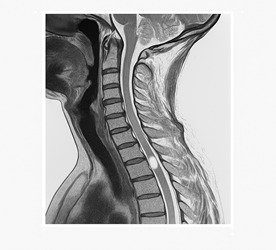

Imaging studies (Figures 1 and 2 as shown):

Figure 2: Demonstrated cerebral atrophy which is normal for his age, with no acute pathological changes, thus excluding central nervous system causes.

5. Brainstem stroke

Clinical consideration: initially considered due to the acute onset of facial weakness and bulbar symptoms that could suggest brainstem pathology.

Exclusion criteria: normal brain CT scan, excluding acute cerebrovascular events, bilateral symmetrical presentation rather than focal neurological deficits peripheral nerve involvement demonstrated on electrophysiology.